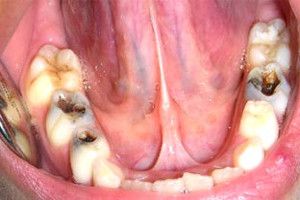

En nuestra Clínica, son muchos los padres que nos preguntan el porqué empastar los dientes de leche si se van a caer. La respuesta siempre es clara y firme, SÍ HAY QUE EMPASTAR LOS DIENTES DE LECHE, ya que cualquier infección en un diente de leche, puede llegar a afectar al diente definitivo, provocando manchas, malformaciones…

Además, el no tratar una caries en un diente de leche puede provocar dolor, y hacernos tener que extraer ese diente antes de tiempo, provocando alteraciones en la mordida, que harán que necesitemos tratamientos de ortodoncia para corregir la malposición de los dientes definitivos como consecuencia de la perdida prematura del diente de leche.